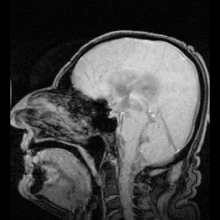

إذا كانت الفتحة في البطين الرابع أو القناة الدماغية قد أغلقت، فإن السائل النخاعي سيتراكم في البطينات. تسمى هذه الحالة استسقاء الرأس الداخلي ويسبب هذا ارتفاعاً في ضغط السائل النخاعي. انتاج السائل النخاعي سيستمر، حتى لو كان هناك إغلاق في امتصاص السائل النخاعي إلى الدورة الدموية خارج الدماغ. وبالتالي، السائل النخاعي سيتراكم داخل الدماغ، مسبباً بذلك توسع البطينات الدماغية وضغط على النسيج العصبي. عادة يؤدي الضغط على النسيج العصبي إلى تلف لا يمكن استرجاعه. إذا لم تكن عظام الجمجمة قد أكملت تحجرها والتحامها أثناء حدوث استسقاء الرأس، فإن توسع الرأس بشكل كبير سينتج من ارتفاع الضغط أيضاً. القناة الدماغية يمكن أن تكون مسدودة عند وقت الولادة أو تنسد في وقت لاحق في الحياة بسبب نمو ورم في جذع الدماغ.

في الأطفال الذين يعانون من استسقاء الرأس، السائل النخاعي يتراكم في الجهاز العصبي المركزي مما يتسبب في انتفاخ اليافوخ (بقعة لينة)، والرأس يصبح حجمه أكبر مما هو متوقع. ومن الأعراض التي يمكن أن تظهر في وقت مبكر: